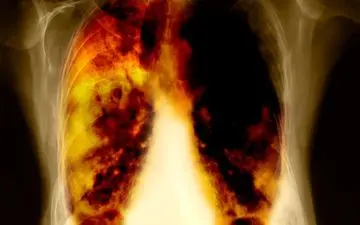

مطالعه مشاهده ای اخیر نشان می دهد که پیروی از یک رژیم غذایی کم چرب ممکن است به کاهش خطر ابتلا به سرطان ریه کمک کند.

مطالعه جدید نشان می دهد رژیم غذایی سرشار از گوجه فرنگی و میوه، بخصوص سیب، به بازیابی آسیب ریوی ناشی از سیگارکشیدن کمک…